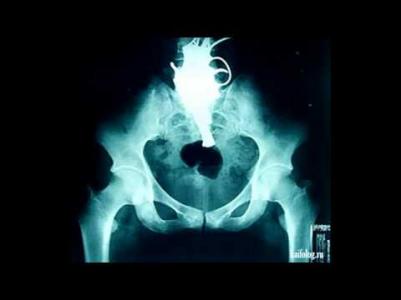

Мальчику удалили 26 магнитных шариков из мочевого пузыря (3 фото)

Китайским врачам пришлось провести двухчасовую операцию по удалению цепочки из 26 магнитных шариков, которые 11-летний мальчик засунул в свой пенис "из любопытства". Ребенок начал страдать от боли, гениталии распухли, появилась кровь при мочеиспускании (не мудрено, в общем-то). Ситуация была непростая, и эндоскопические методы не сработали.

Имя мальчика не называется, а операцию провел хирург-педиатр Вонг Юнбяо в детской больнице в Вэнчжоу (провинция Чжэцзян). По его словам, шарики образовали две цепочки и застряли в области задней уретры. Сложность ситуации заключалась в том, что диаметр такого магнитного шарика составляет 3 мм, и когда они образовали двойную цепочку, это было уже целых 6 мм.

Врач решил протолкнуть шарики в мочевой пузырь, а затем удалить их по одному с помощью специальных щипцов для цистоскопии, чтобы избежать блокировки мочеиспускания. Доктор Вонг попытался извлечь щипцами 26 шариков один за другим, однако в мочевом пузыре они слиплись в один большой комок и их невозможно было разделить. Пришлось проводить цистостомию - хирургическую операцию на мочевом пузыре.